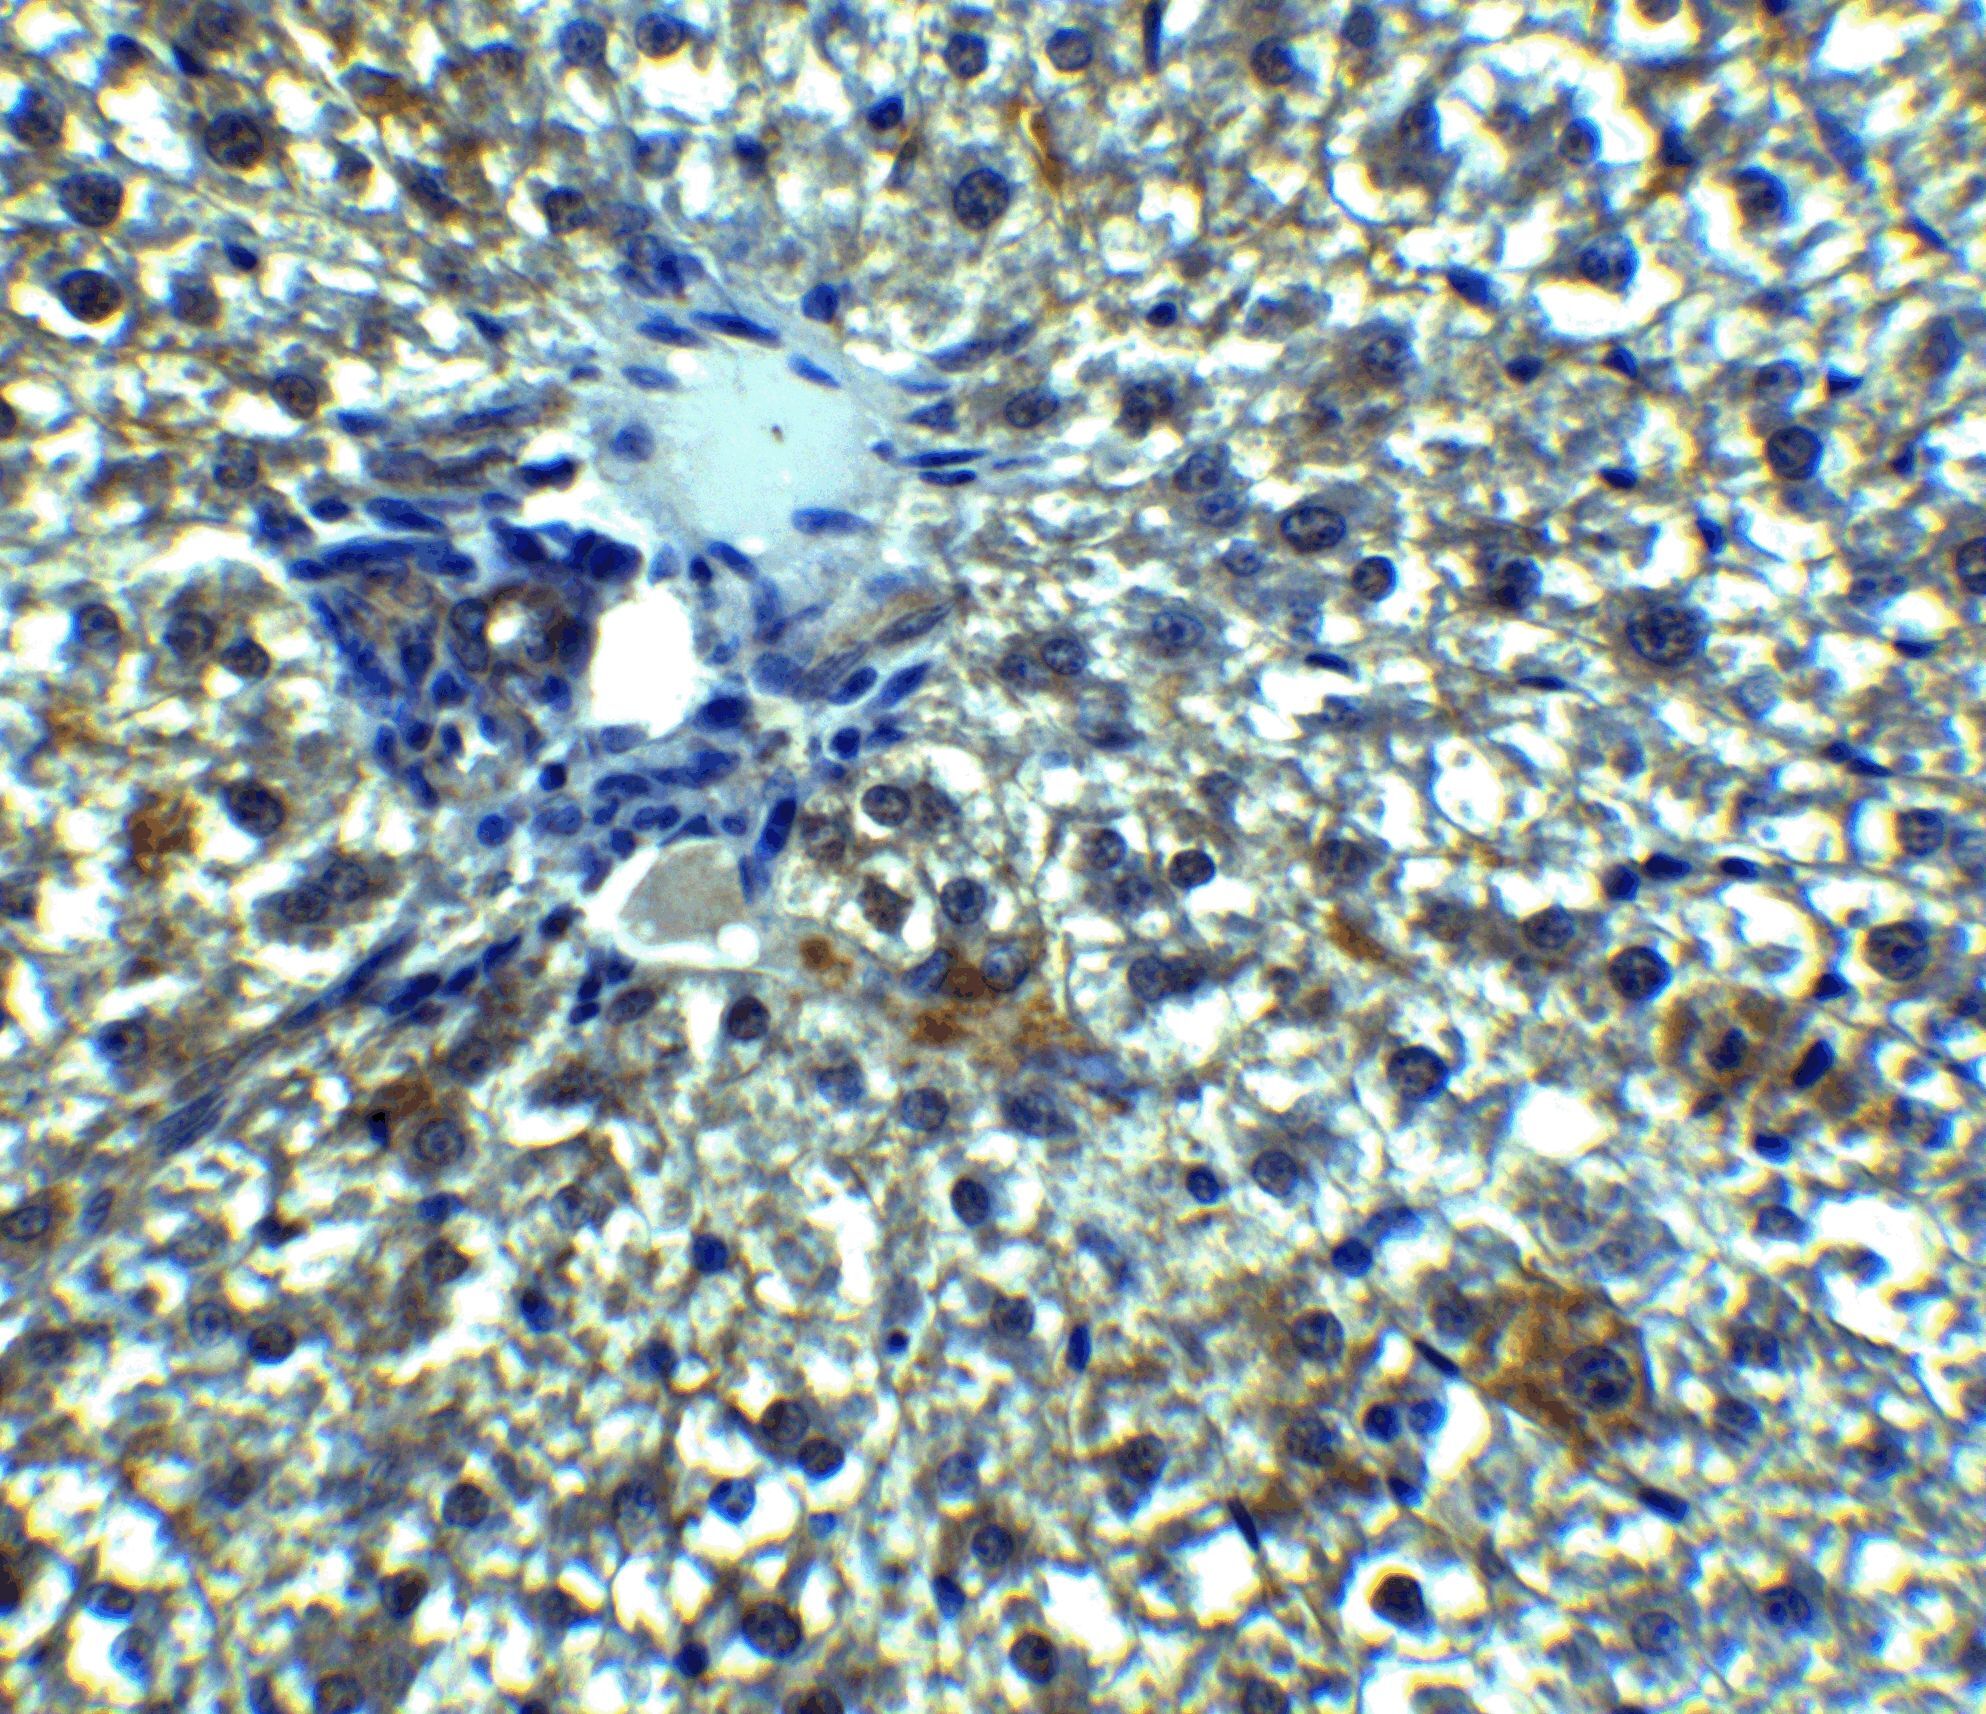

- Submitted by

- Invitrogen Antibodies (provider)

- Main image

- Experimental details

- Immunohistochemistry of Betatrophin in mouse liver tissue with betatrophin Polyclonal Antibody (Product # PA5-38043) at 5 µg/mL.